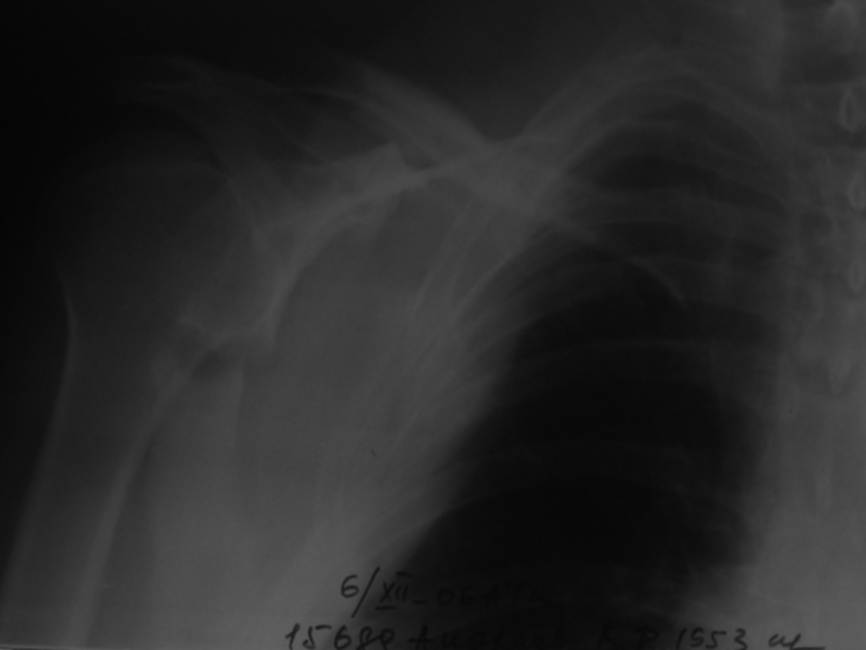

Уважаемые коллеги, помогите определиться с тактикой. Больной 1953гр, травма на стройке, придавило тяжелымпредметом. Сейчас в сознании, стабилен, плевральная полость задренирована. Предполагаем синтез ключицы, если бы не переломы ребер, установили бы шину ЦИТО.Есть у кого опыт открытого/закрытого синтеза подобной лопатки? Что делать с клювовидным отростком? Спасибо, Моисеев Ю.И.

Очень интересно, если есть рентген ребер покажите.С уважением Дрягин